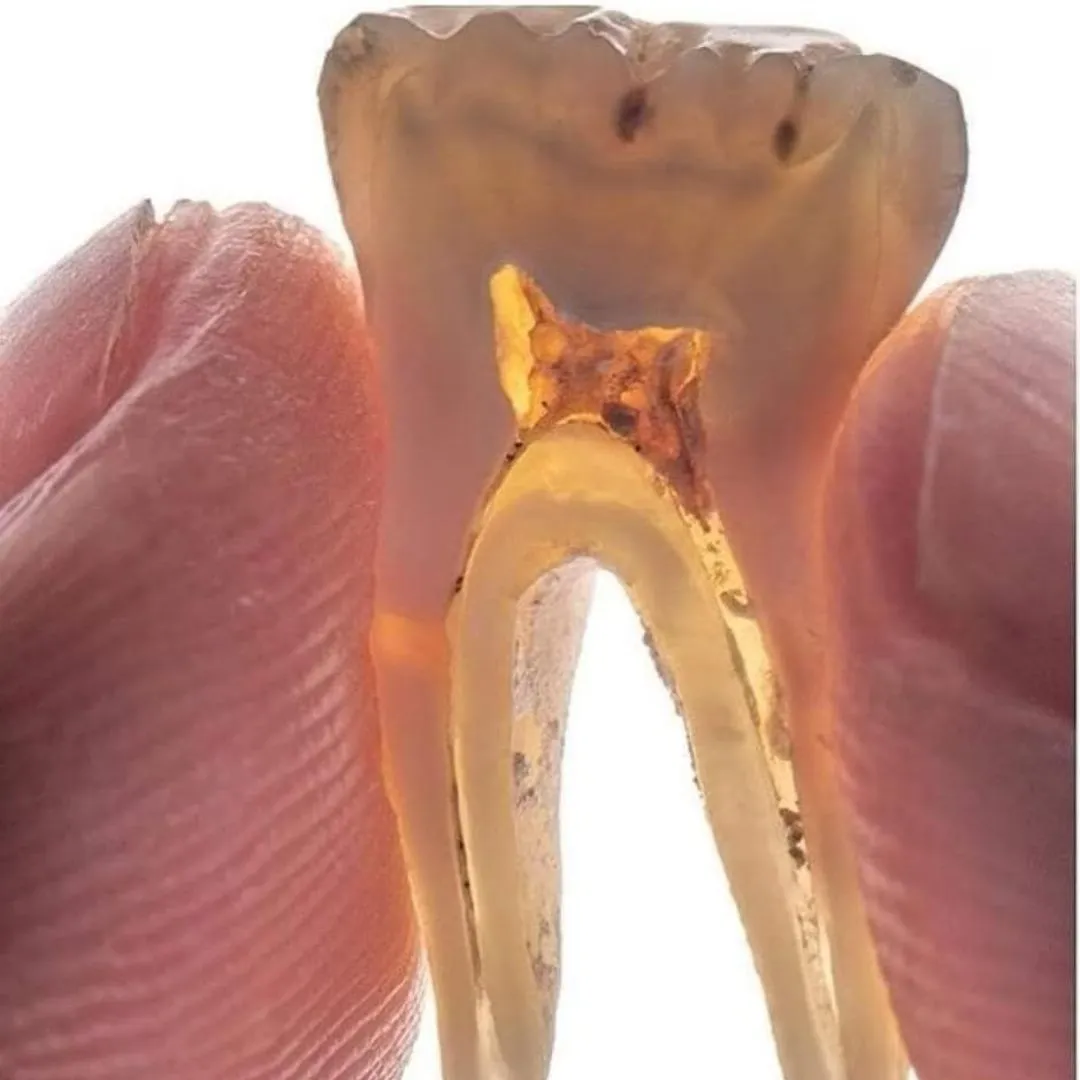

If you're anxious about dental treatment, don't hesitate. Visit JP dental ,Perambur! Dr. Jayaprakash is exceptional, especially with nervous patients like my mom, who had delayed root canal treatment for over 2 years. He showed remarkable patience and tailored the treatment to her comfort. We're extremely satisfied with the service, reasonable charges, and friendly atmosphere. The care is pain-free and worth every penny. Highly recommended!

After searching dentist near me ,I visited JP Dental ,Perambur,.This clinic keeps a clean and hygiene space , sterilizing tools, and having modern equipment like digital X-rays for precise, germ-free work.Dr. JP was super nice, explained everything easy, and my root canal didn't hurt at all.I personally recommend for everyone.